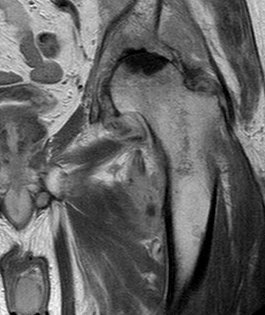

MRI is very sensitive but may still struggle to differentiate between advanced sepsis and AVN.